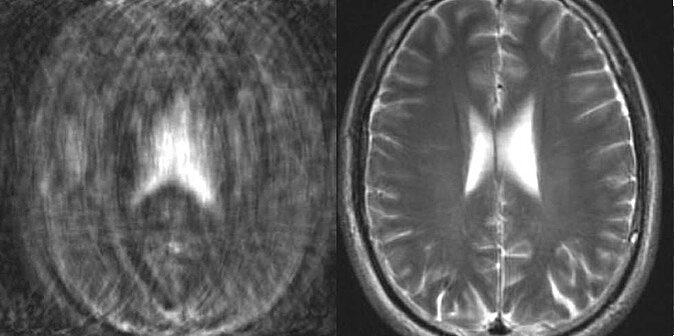

Фото из открытых источников

Артефакты – это ложные сигналы, которые можно назвать дефектами на снимках (могут выглядеть как затемнение, полоса, искажение). Они возникают из-за дыхания и сердцебиения, движений пациента, а также из-за металла в его теле.

КТ-аппараты не чувствительны к ферромагнитным металлическим частям в теле пациента, быстрее делают снимки с меньшей толщиной среза и позволяют с помощью настроек программы обработать сигналы и убрать артефакты. То есть КТ умеют корректировать артефакты.

МРТ нельзя применять при наличии в теле пациента любых ферромагнетиков (они магнитятся от внешнего магнитного поля). Проблемой здесь являются также все физиологические артефакты: от движения, сердцебиения, пульсации крови и спинномозговой жидкости.